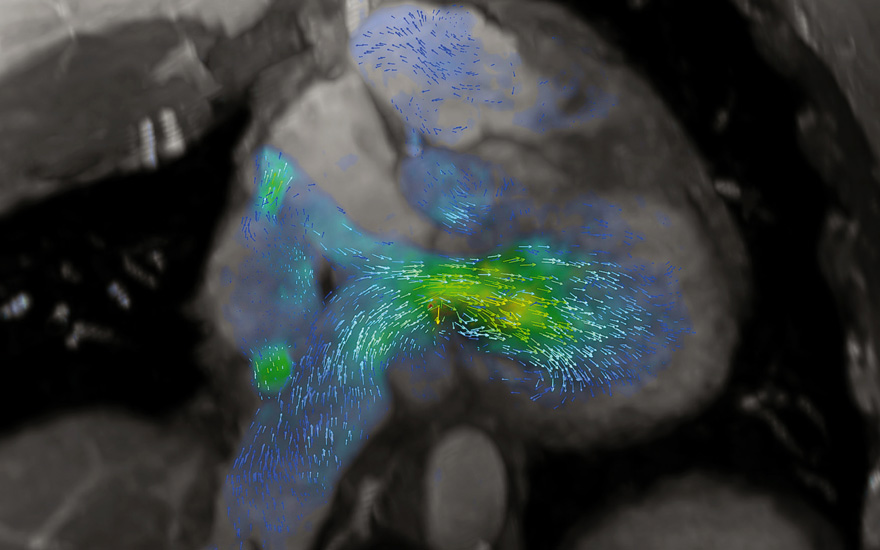

Imagen de la secuencia 4D flow de una transposición de grandes arterias.

Junto con el apoyo de la inteligencia artificial, también se va a presentar las secuencias de imagen cardiovascular denominadas 4D flow que permiten valorar el flujo sanguíneo de cualquier vaso en tres dimensiones durante un ciclo cardiaco. "Gracias a esta herramienta podemos estudiar la dirección y el volumen de flujo, de los vasos, la velocidad pico, gradientes de presión y la fracción de regurgitación de una forma muy visual y cuantificable, lo que nos ayuda a estudiar fácilmente patologías como la comunicación interauricular, la interventricular, los ductus arteriosos, cualquier patología valvular; las afecciones de la aorta, como los aneurismas o las disecciones, y las malformaciones congénitas", detalla el doctor Martínez de Vega,